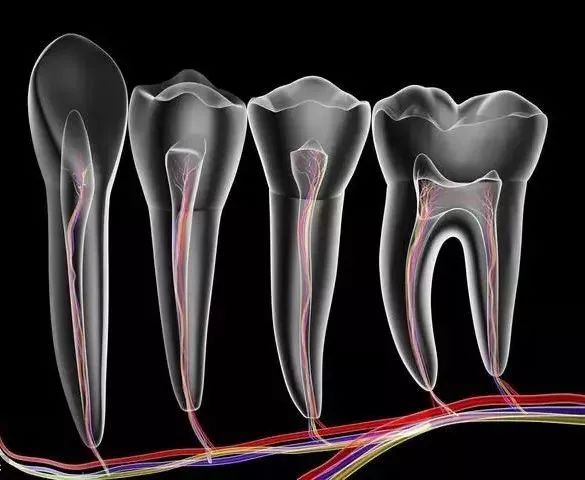

这是目前最有效、最常见的治疗牙髓病和根尖周病的方式,可以消除牙齿内部炎症及其病变源,

其过程就是先将牙齿内部坏死的牙髓清理干净,再放入永久性消炎杀菌的药物,

第一步:开髓

先在牙齿上开一个直通内里、 方便操作的大门。

第二步:杀神经

出了问题的牙神经会在牙齿内部腐坏、发酵,造成严重的感染和疼痛。

所以,我们需要将牙神经杀死,然后和坏死的组织一起清理出来,来消除炎症。

第三步:填充

放入永久性消炎杀菌的药物,对根管进行严密填充,保证根管之后不会再出现炎症。